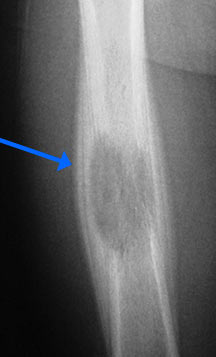

- May arise from any bone and any site within a bone (epiphyseal, metaphyseal, diaphyseal)

- Radiographically variable appearance: may appear benign (geographic) or malignant (permeative or moth eaten)

- Flat Bones (most common—70%)

- Femur

- Humerus